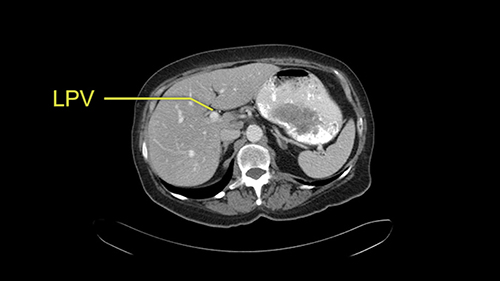

![[RHA]](jpg/preop_sg_moment3.jpg)

The only other most important feature that I usually consider is the portal vein split or the bifurcation, especially if doing a major liver resection like a right lobe. I like to look at the length of the common right portal vein trunk which looks like its probably long enough to put a stapler on. Final decision would be in the OR. If it wasn’t long enough and I was concerned about injuring the bifurcation or the left portal vein, then I would divide the Segment 5-8 and 6-7 portal tracks individually.

![[LPV]](jpg/preop_sg_moment4b.jpg)